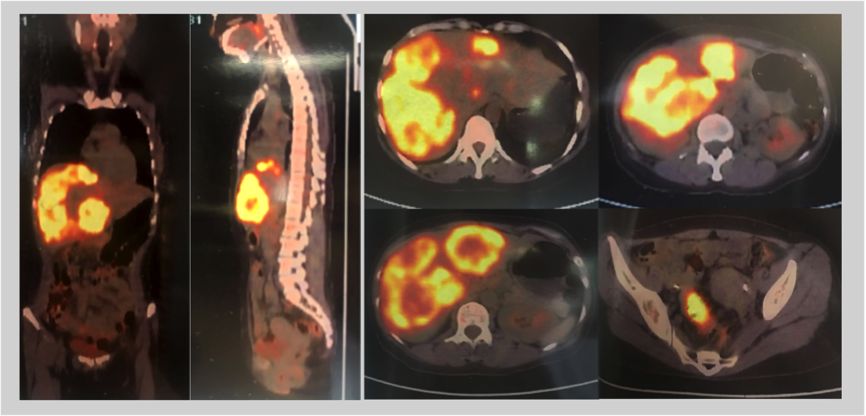

2017-10-30 PET-CT:1. 乙状结肠肠壁走形不均匀增厚、僵硬,FDG代谢异常增高,考虑恶性病变。周围肠系膜内多发稍增大淋巴结伴FDG代谢增高,考虑淋巴转移可能。2. 肝内见弥漫软组织块状影伴坏死,FDG代谢增高,考虑肝内转移。

PET-CT提示:乙状结肠淋巴转移,肝内转移。